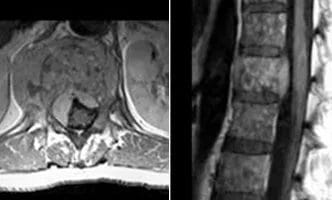

A patient with known breast cancer presents with lower back pain.

There is a large metastatic mass in T12 with extra osseous extension into the paravertebral tissues and intraspinally. The lesion is clearly identified on both the sagittal and axial post contrast sequences.